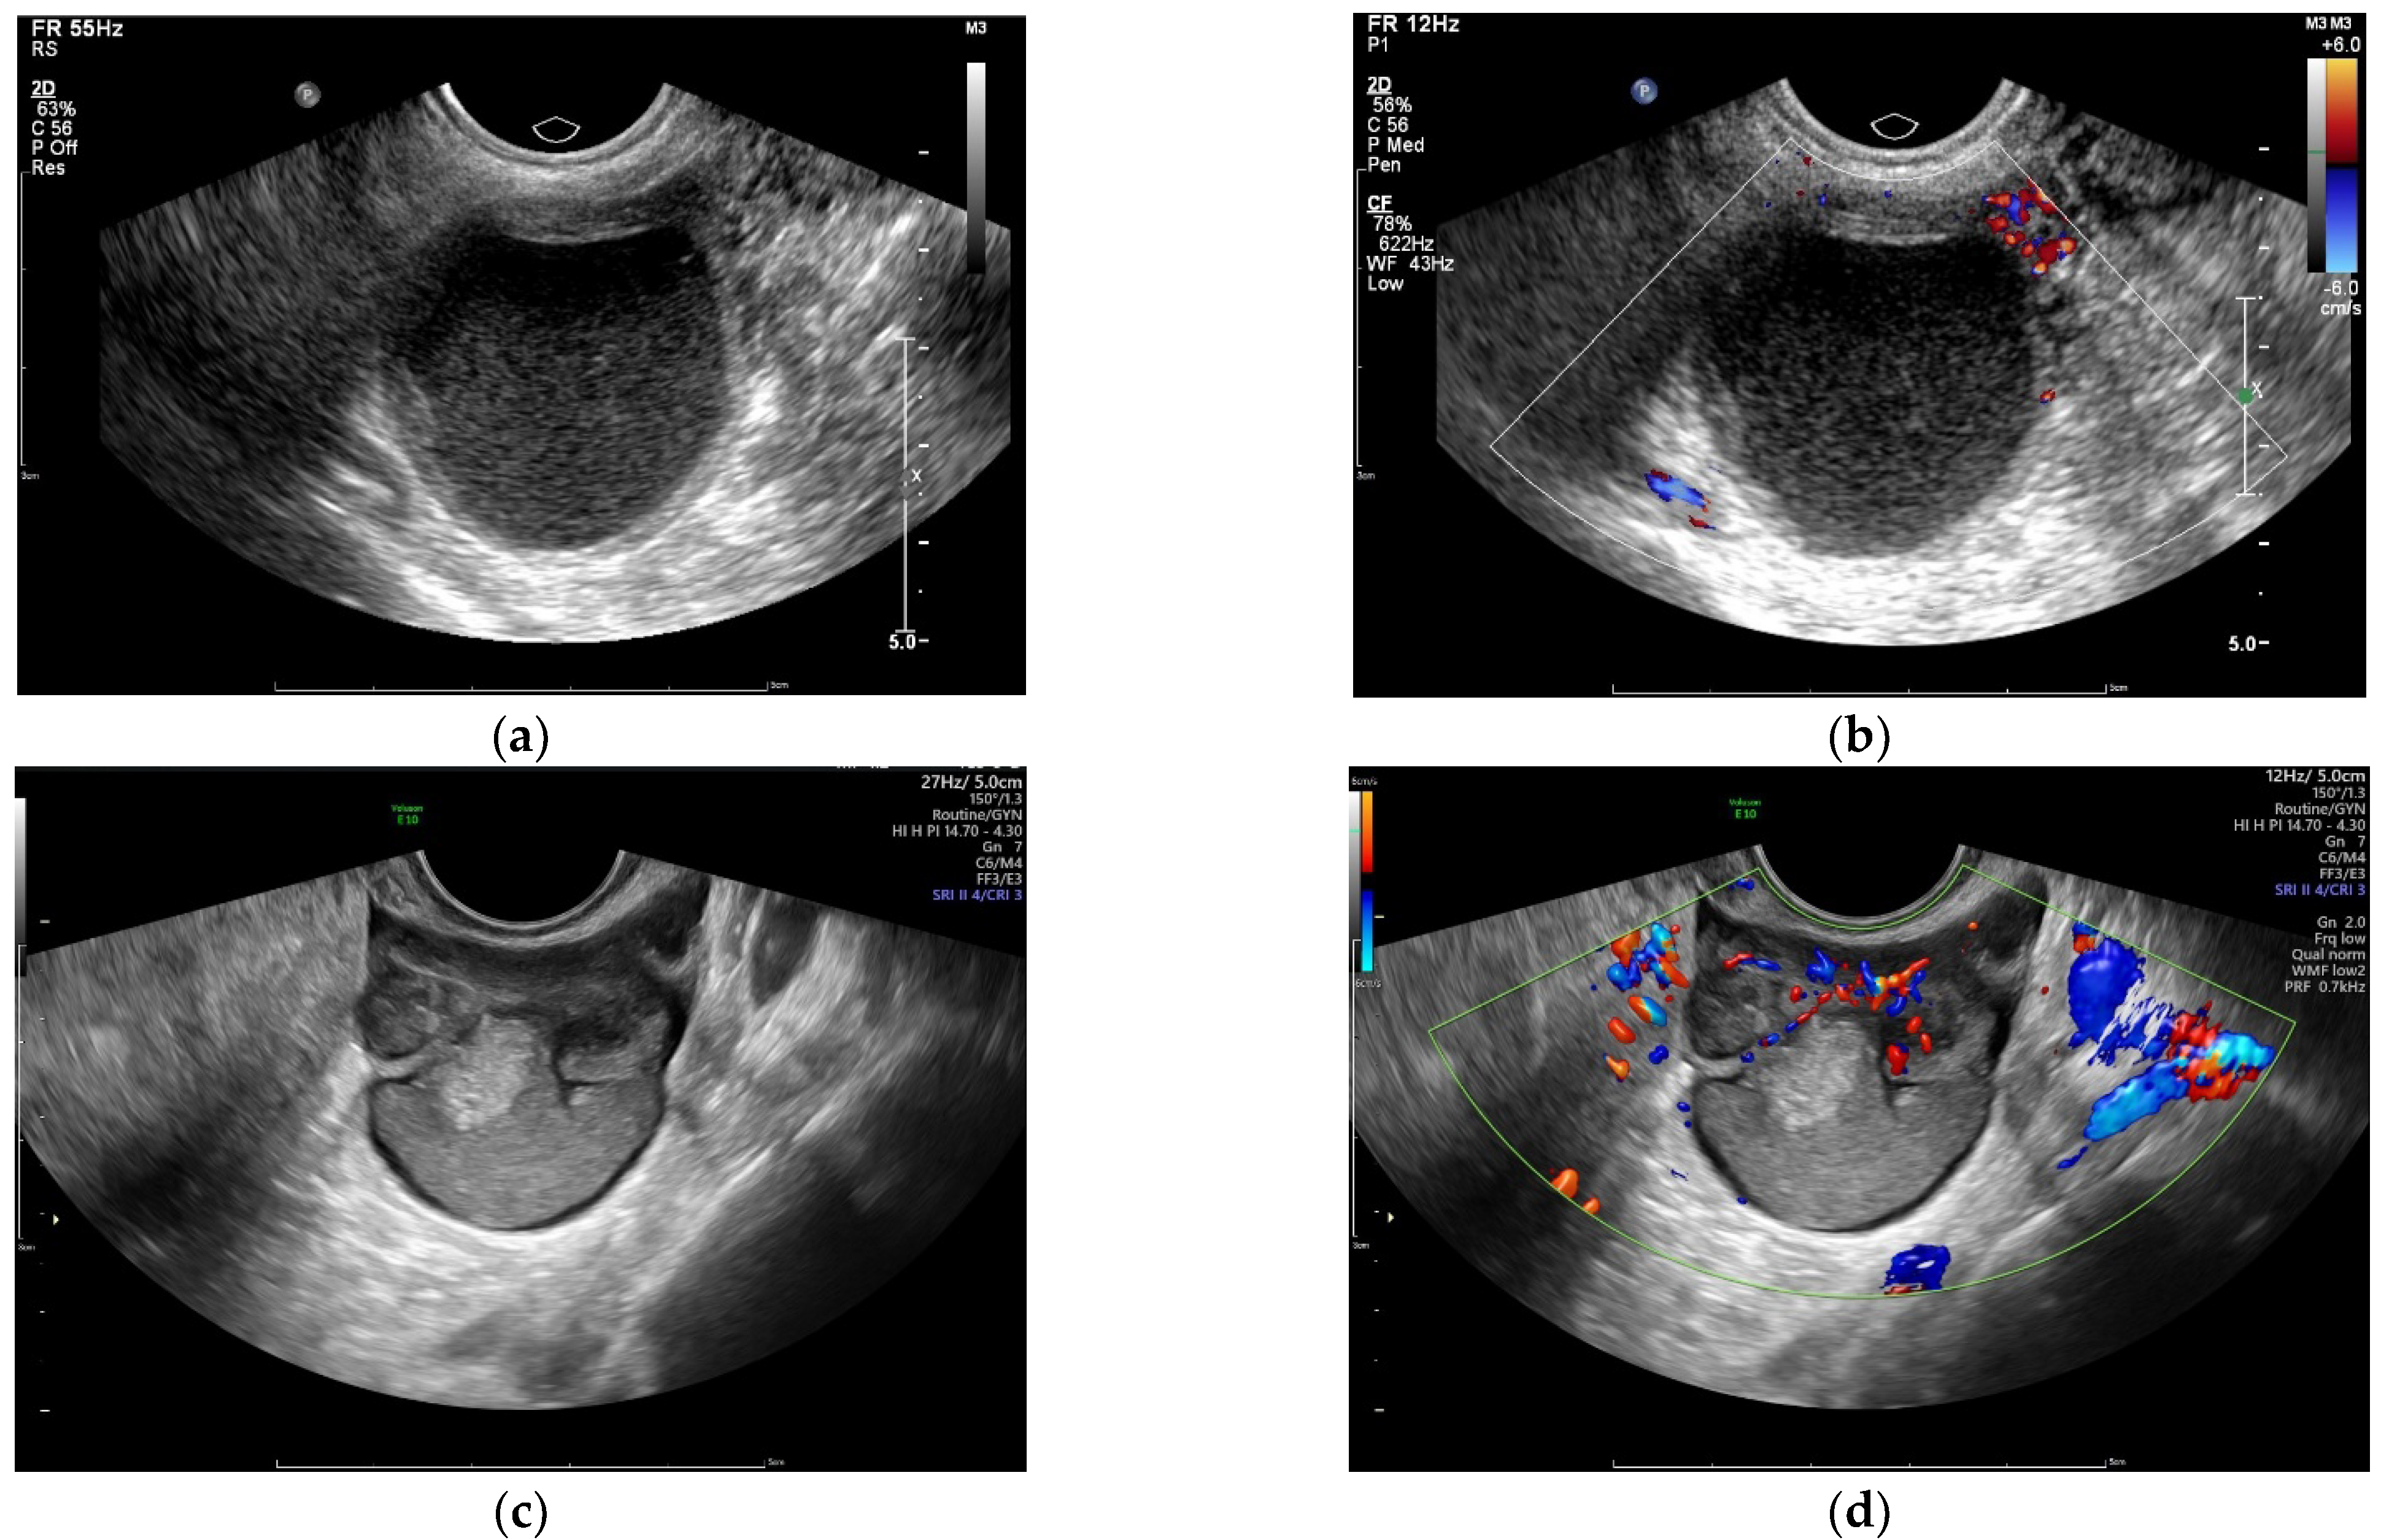

2.2. Sonography

3.3.1. Sonographic Parameters

| Endometrial cysts ** | Unilateral | 151 (91.5%) | 177 (54.3%) | <0.001 |

| Bilateral | 14 (8.5%) | 149 (45.7%) | ||

| Adenomyosis ** | 23 (13.9%) | 145 (44.5%) | <0.001 | |

| 142 (86.1%) | 181 (55.5%) | |||

| Pelvic endometriosis nodules ** | Yes | 14 (8.5%) | 96 (29.4%) | <0.001 |

| No | 151 (91.5%) | 230 (70.6%) | ||

| Unilocular cyst | Yes | 103 (62.4%) | 162 (49.7%) | 0.008 |

| No | 62 (37.6%) | 164 (50.3%) | ||

| Color Doppler flow | Without | 102 (61.8%) | 199 (61.0%) | 0.868 |

| With | 63 (38.2%) | 127 (39.0%) | ||